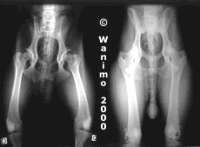

Le vétérinaire peut

suspecter cette maladie chez

un chien par un examen

rapproché des membres. Le

diagnostic de certitude est

posé grâce à la

radiographie. Cette

radiographie est réalisée

après l'âge de un an 18

mois chez les races géantes

comme le dogue allemand),

car avant, on risque de ne

pas détecter la maladie.

Le chien est alors classé

parmi les cinq catégories,

allant de A à E, A étant

l'absence de dysplasie et E

la forme la plus avancée

(la tête du fémur est

alors complètement luxée).